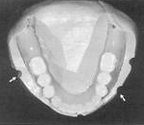

Existing complete denture on trimmed silicone putty cast. Note multiple notches scored on borders of putty cast (arrows) A, Sectioned silicone mold over area of anticipated implant positions engaging multiple notches. Space limitation can be measured before implant surgury. B, Anticipated independant implant over denture attachment can be "tried in" by turning upside down to fit within space.